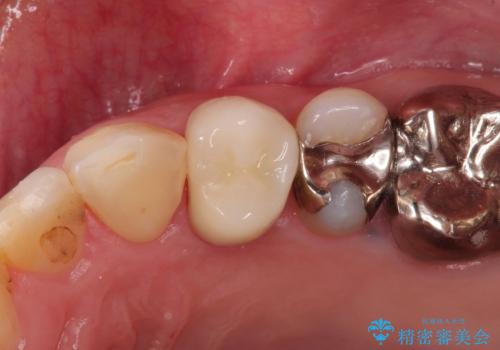

総合歯科治療 → 根管治療&セラミック治療

セラミックインレーと根管治療を伴うセラミッククラウン